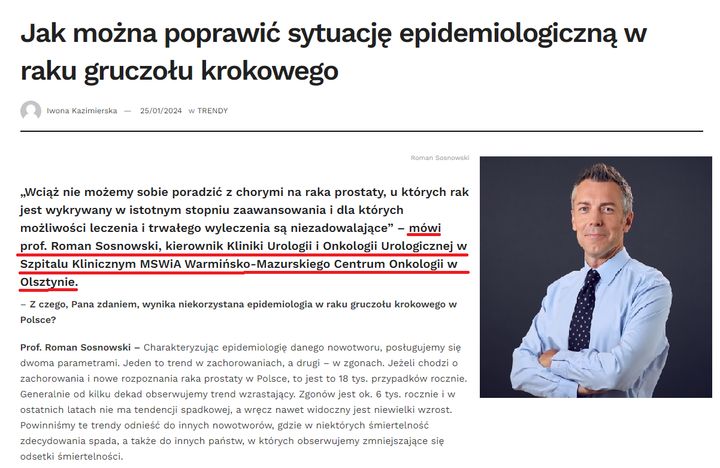

Zapraszamy do lektury wywiadu z lekarzem urologiem dr. hab. n. med. Romanem Sosnowskim.

„Wciąż nie możemy sobie poradzić z chorymi na raka prostaty, u których rak jest wykrywany w istotnym stopniu zaawansowania i dla których możliwości leczenia i trwałego wyleczenia są niezadowalające” – mówi prof.